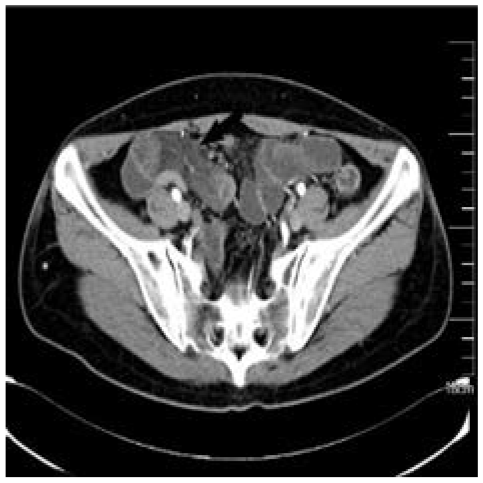

Patient B, a 52-year-old woman, went to the hospital on 3 November 2020 because of “recurrent upper abdominal pain for more than 20 days”. The patient had abdominal pain more than 20 days ago. The pain was mainly in the middle and upper abdomen, which was like a paroxysmal knife cutting and relieved after several seconds. There was no radiating pain in the waist and back, no abdominal distension, and no nausea and vomiting. Physical examination showed tenderness in the middle and right upper abdomen without rebound pain and muscle tension. The abdomen is flat without gastrointestinal type or peristalsis wave, there was no obvious mass, and the bowel sounds are normal. Admission diagnosis revealed abdominal pain of unknown origin. There were no abnormalities in blood routine, CRP, biochemistry, AFP, CA19-9, and CEA. Abdominal enhanced CT showed local intestinal wall edema, structural disorder, and mesenteric edema, as shown in Figure 4. Esophagogastroduodenoscopy revealed bile retention fluid in the stomach. Capsule endoscopy showed ileal lesions, with multiple continuous nodular changes in the mucous membrane, and the surface was red and erosive, as shown in Figure 5. Contrast-enhanced CT of the small intestine showed segmental intestinal wall thickening in the terminal ileum with obvious edema of the surrounding mesentery, which suggested the possibility of inflammatory bowel disease (IBD). CT three-dimensional reconstruction of small intestine showed segmental intestinal wall thickening in the distal ileum with obvious edema in the surrounding mesangium. After consultation with the imaging department, the patient was suspected to have Crohn’s disease (CD) due to the ileal lesions. However, the clinical features and course of the patient did not conform to the typical manifestations of CD, so surgical treatment was important for diagnosis and treatment. The patient underwent surgical treatment on 1 December 2020. Intraoperative exploration revealed a 30-cm-long part of the small intestine with obvious edema and thickening 4.5 m away from the ligament of Treitz. The intestinal lumen was narrow and the mesangial surface was uneven, showing cystic jelly-like changes. During operation, the operator dissected a piece of intestine with a length of 38 cm and a diameter of 4–7 cm. There is an 11 cm × 7 cm mucous bulbous area 6.5 cm away from the cut end on one side and 15 cm from the cut end on the other side. The mesenteric surface was hard in texture, and the cut surface was spongy and gray yellow, as shown in Figure 6. Pathology indicated small intestinal lymphangioma, and no cancer involved both ends, as shown in Figure 3. After the operation, she left the hospital after receiving anti-inflammatory and nutritional support therapy.

Figure 4 CT of patient B’s abdomen. Pelvic local intestinal wall edema, disorder, and mesenteric edema.